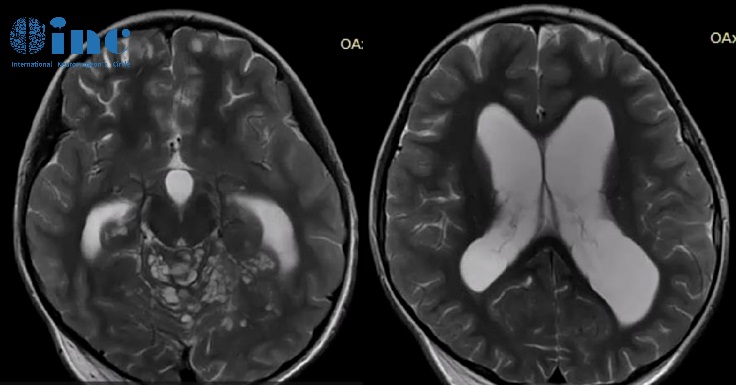

小脑弥漫性可见多发囊性病变,特别是上叶正中区和上蚓部,可能导致脑脊液循环障碍伴继发性脑室扩张。

从文献中提取的一些图像说明了刚才提到的情况:增强的蛛网膜的病理性增粗,肿瘤的多个结节状定位,相关的脑积水。大脑的非强化局灶性囊性病变是由血管周围间隙的局灶性扩大造成的,也是因为脑脊液循环受阻而扩大。

基于临床的资料(年龄、性别、非不同性的神经表现、脑积水)和神经放射学影像(特征性的颅内和椎管内结节性脑胶质增粗和强化,常伴有小囊性的非强化病变,蛛网膜下腔和室管膜表面的涂层),我可以确认弥漫性软脑膜胶质神经元肿瘤的诊断。